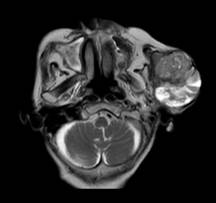

Hình ảnh khối u trên phim cộng hưởng từ

Cụ bà L.T.C nhập viện trong tình trạng có khối u lớn vùng mặt bên trái, gây đau, biến dạng khuôn mặt và ảnh hưởng nhiều đến sinh hoạt trong suốt nhiều năm. Kết quả sinh thiết xác định đây là ung thư biểu mô tế bào đáy dạng tuyến nang (adenoid type) - một thể hiếm gặp của ung thư da.

TS.BSCKII Nguyễn Quang Hưng - PGĐ, Trưởng khoa Ngoại Đầu Mặt Cổ là người trực tiếp mổ chính ca bệnh. Ca phẫu thuật diễn ra trong sự cẩn trọng từng thao tác và đã hoàn thành thuận lợi. Khối u được cắt bỏ rộng rãi, đồng thời bảo tồn các cấu trúc quan trọng như dây thần kinh mặt và ống tuyến mang tai, đảm bảo chức năng cũng như tính thẩm mỹ cho người bệnh.